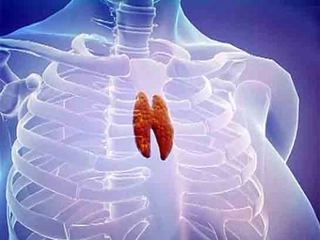

Beze, tıpta "hidradenit suppurativa" olarak bilinen, genellikle ciltte iltihaplı nodül ve apselerin oluşumuyla karakterize bir hastalıktır. Bu durum, özellikle ter bezlerinin yoğun olduğu bölgelerde, yani koltuk altı, kasık, kalça ve meme altı gibi yerlerde meydana gelir. Beze, genellikle ciltte ağrılı lezyonlar, iltihap ve kötü bir koku ile birlikte seyreder. Bu makalede, bezelerin belirtileri, tanı yöntemleri ve tedavi seçenekleri detaylı bir şekilde ele alınacaktır. Beze BelirtileriBeze belirtileri genellikle aşağıdaki şekilde sıralanabilir:

Ek BilgilerBeze, genetik, hormonal ve çevresel faktörlerin etkileşimi sonucunda ortaya çıkabilen bir hastalıktır. Özellikle aile öyküsü bulunan bireylerde hastalığın görülme sıklığı artmaktadır. Bunun yanı sıra, kadınlarda erkeklere göre daha sık rastlanmaktadır. Hastalığın tedavisinde erken müdahale büyük önem taşımaktadır; bu nedenle, belirtiler görüldüğünde bir dermatologa başvurmak önemlidir. Sonuç olarak, beze belirtileri ve tedavisi üzerine yapılan araştırmalar, bu hastalığın cilt sağlığını önemli ölçüde etkilediğini göstermektedir. Tedavi yöntemleri arasında erken tanı ve bireyselleştirilmiş yaklaşımlar, hastaların yaşam kalitesini artırmakta önemli bir rol oynamaktadır. |